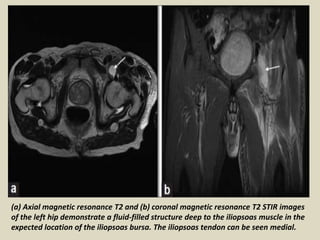

Iliopsoas bursa

The iliopsoas bursa is the largest bursa around the hip joint (average

size, 6 cm × 3 cm) and is situated beneath the musculotendinous portion

of the iliopsoas muscle, anterior to the hip joint capsule and lateral to

the femoral vessels. It is found in about 98% of the subjects, and

communicates with the cavity of the hip joint in about 15% of the cases.

Normally collapsed, distension of the bursa is usually caused by

overproduction of synovial fluid in an arthritic hip leading to increased

intraarticular pressure and extension of fluid into the potential space of

the bursa.

(a) Axial magnetic resonance T2 and (b) coronal magnetic resonance T2 STIR images

of the left hip demonstrate a fluid-filled structure deep to the iliopsoas muscle in the

expected location of the iliopsoas bursa. The iliopsoas tendon can be seen medial.